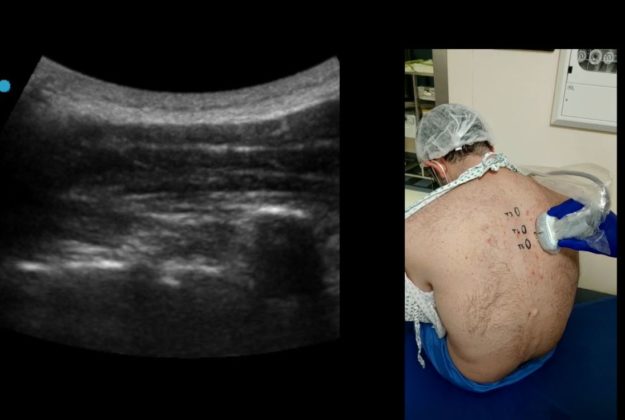

Esistono emergenti evidenze scientifiche sempre più consolidate in merito all’efficacia antalgica/anestetica dei blocchi fasciali in ambito cardiochirurgico. Tra questi, l’ESP block è stato proposto come tecnica anestesiologica di comprovata efficacia…